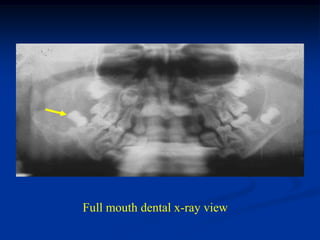

Case #435

4 year female

EG right mandible

Oral photo of submucosal mass

Mandibular view

Full mouth dental x-ray view

Axial CT scan

Photomic